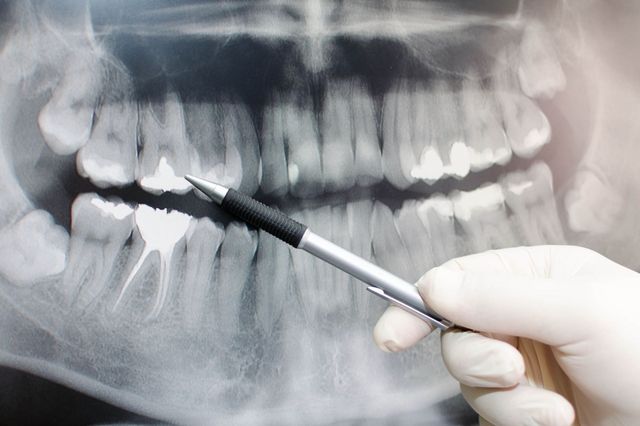

『歯を抜歯しなければいけないと診断されたが、どうしても抜きたくなかった。

抜かずに治療してもらえる歯科医院を転々としているうちに鼻の部屋と口を仕切る硬い壁(骨)に穴があいてしまった』

※これはある患者さんの骨の模型です。右上に穴が空いている部分があります。

上の骨が溶けた場合、上には何があるのでしょうか。

鼻があります、鼻の部屋があるのです。

鼻と口はそれぞれ単体であるものではなく

頭蓋骨をご覧頂くともっとよくわかりますね。

鼻とお口はこうして

繋がっているんです。

「歯を抜かないといけない」と

診断された歯を抜かずに置いておくと鼻の骨まで溶けていきます。

※これはある患者さんの骨の模型です。右上に穴が空いている部分があります。

鼻の骨が溶けたらどうなるのでしょうか?

口と鼻は肉で繋がる状態になります。